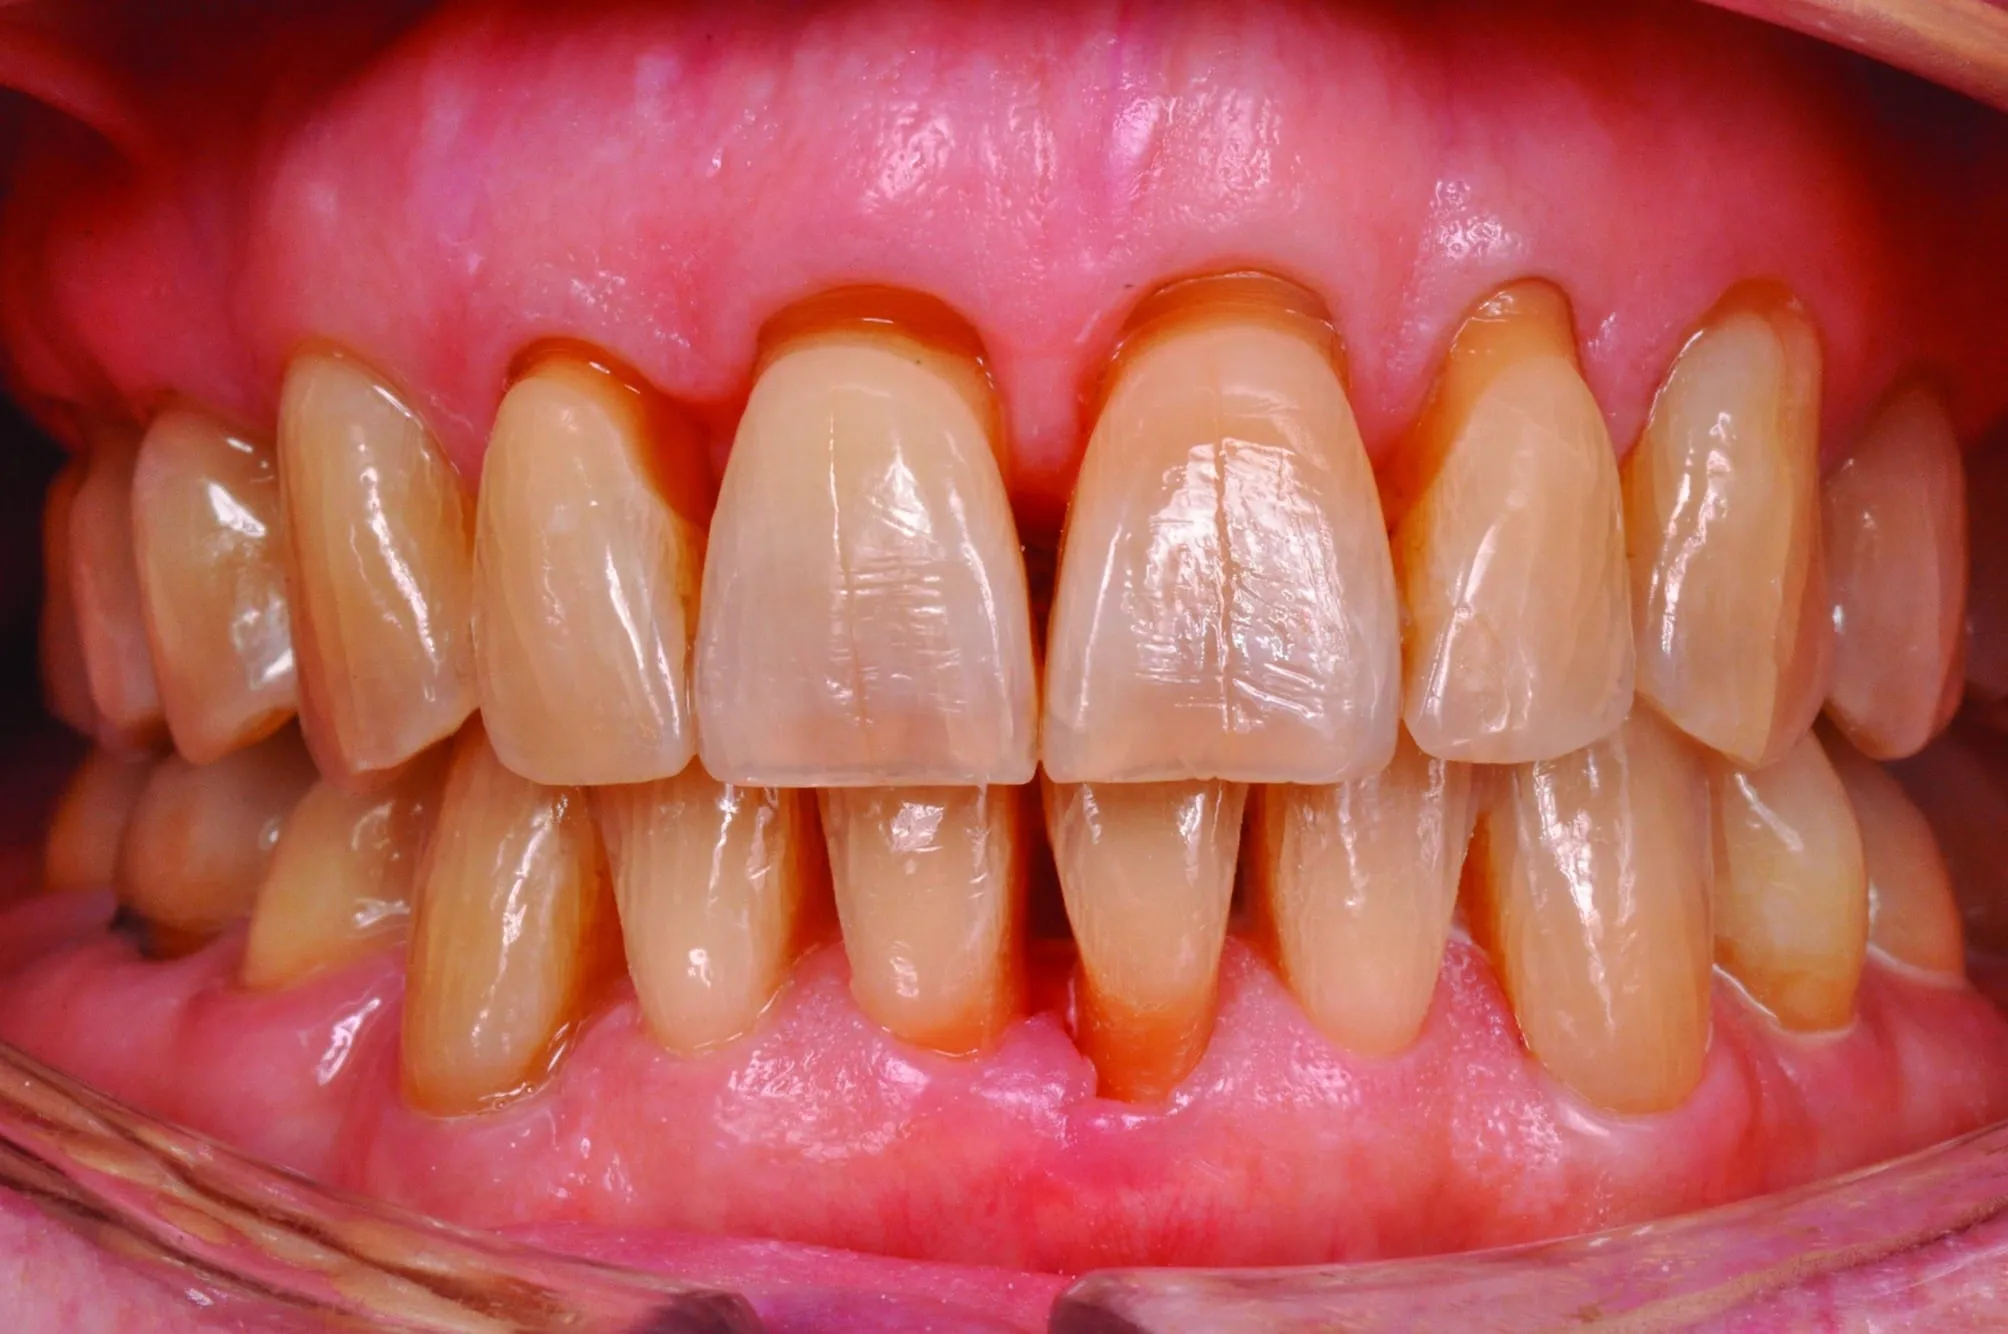

Détartrage & Surfaçage

Nettoyage en profondeur des racines dentaires pour éliminer tartre et biofilm bactérien sous-gingival. Première étape essentielle du traitement parodontal non-chirurgical.